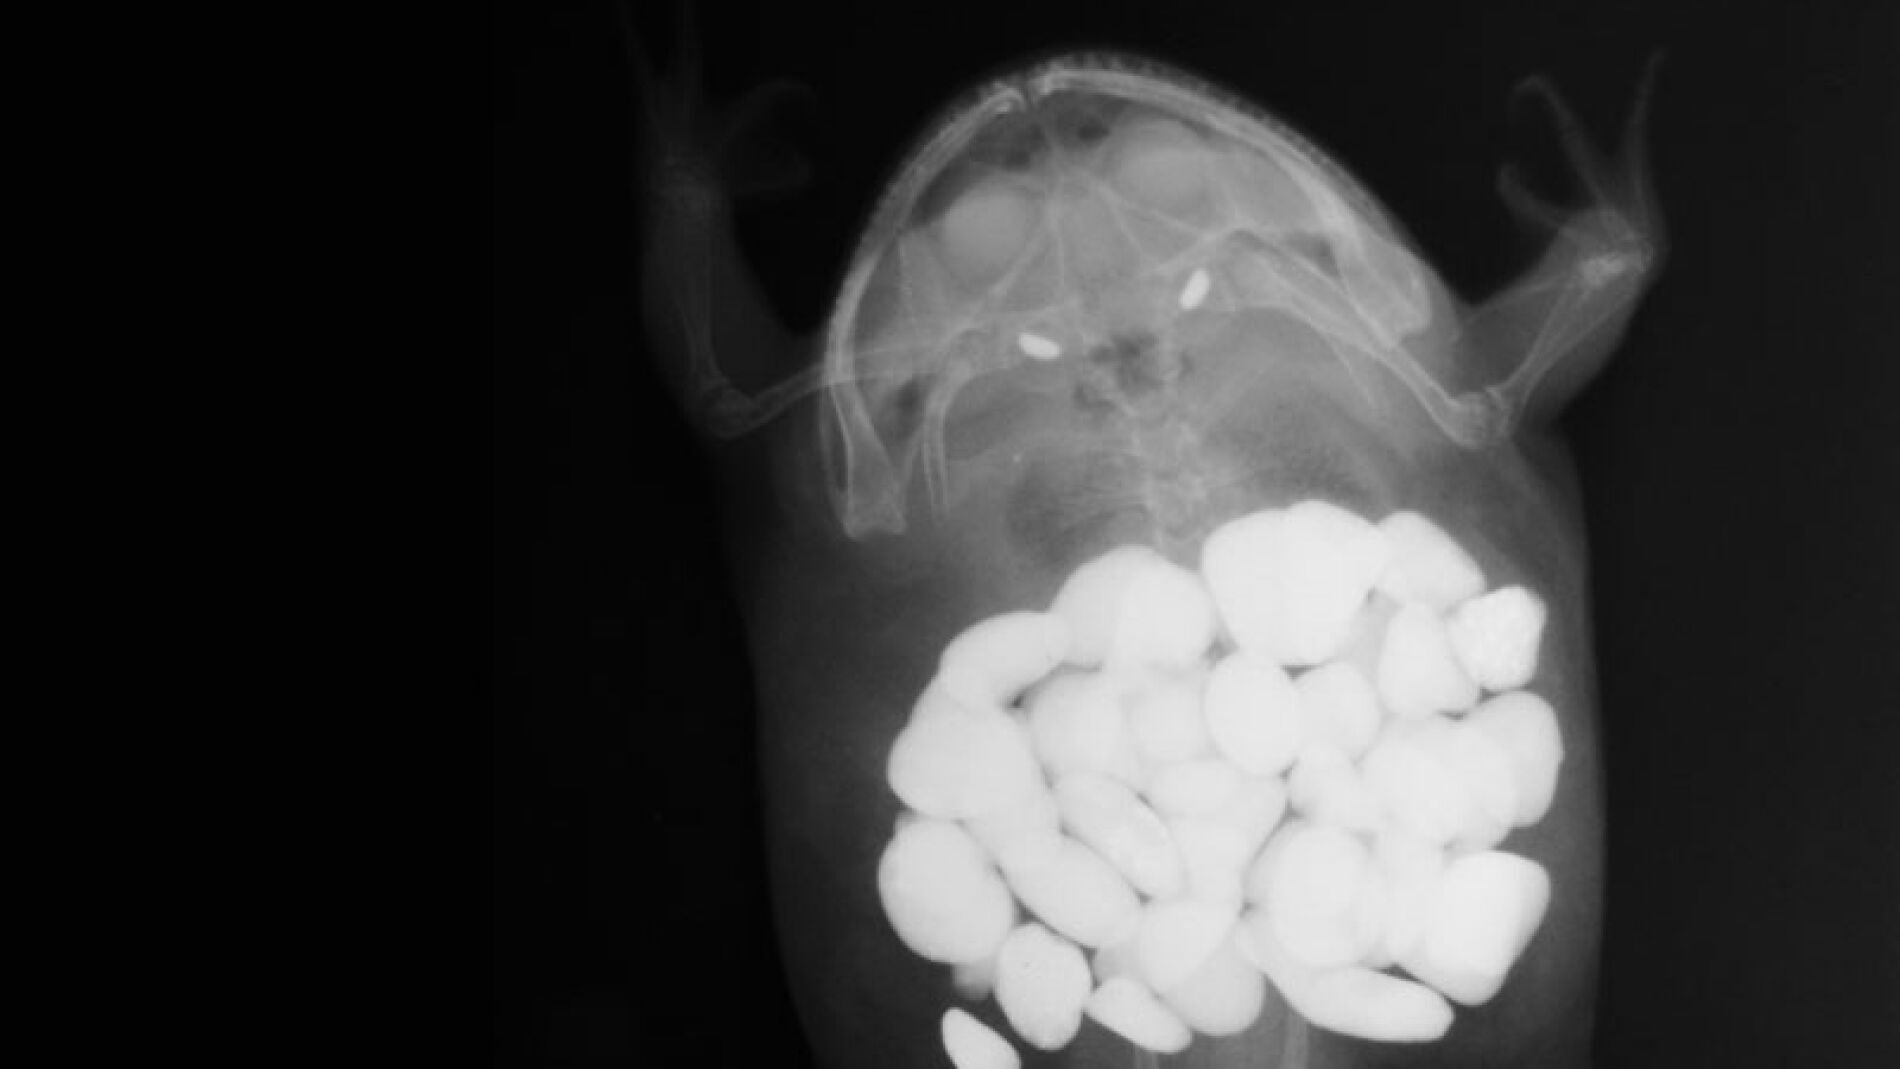

• perros

• gatos